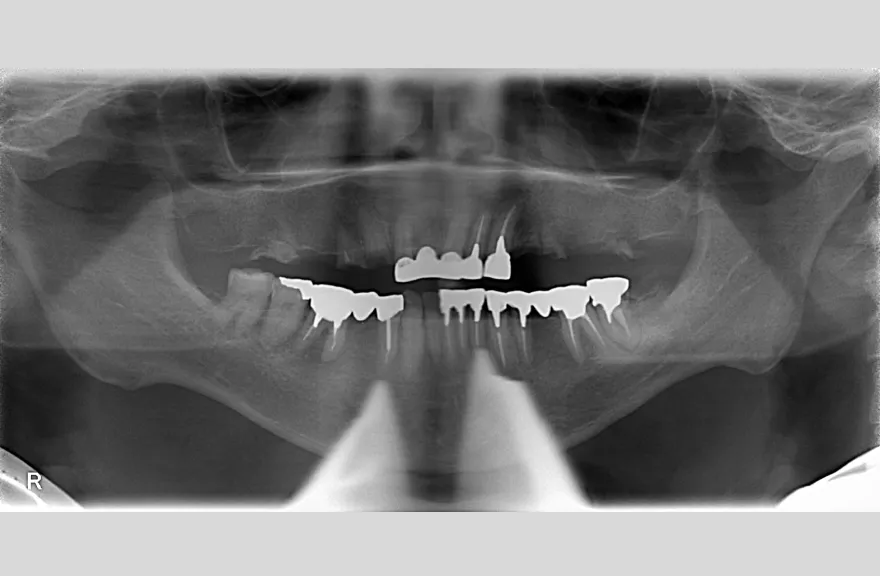

骨格の前後的な差がある方でした。術前のレントゲンより、上下で歯牙の損傷に明らかな差があるのがみてとれます。

上の歯がないところにインプラント治療を行い、上顎は全てインプラントフィクスチャーによる固定性の歯を入れられることも費用的には可能な方でした。

今回の症例では、敢えて上顎は総義歯形態をとり、骨格的な前後の差を解消するよう工夫しました。

上顎の残っていた歯も、差し歯としては使えずとも、敢えて根だけ残すことによって組織を温存し、義歯の安定に寄与するよう設計しました。

ここまで全体的にしっかり治療しておけば、今後の人生においてトラブルになるようなことにはならないでしょう。 - 治療のリスク

上顎の総義歯は、馬蹄形という上顎の覆う部分が小さいタイプで作成いたしました。強度に劣るため、割れる可能性があります。

下顎のクラウン・ブリッジは、丁寧な形成・印象処置と自費専門の技工士によって製作されたもので、虫歯による損傷が今後起こりにくいとは考えますが、定期的なメンテナンスは必須であり、生涯もつものではありません。

神経のない歯(失活歯)は神経がある歯に比べて力が大きくかかりやすく、根が割れたりするリスクがあります。割れ方にもよりますが、基本的には歯が割れてしまうと抜歯処置を行わなければならないことがほとんどです。